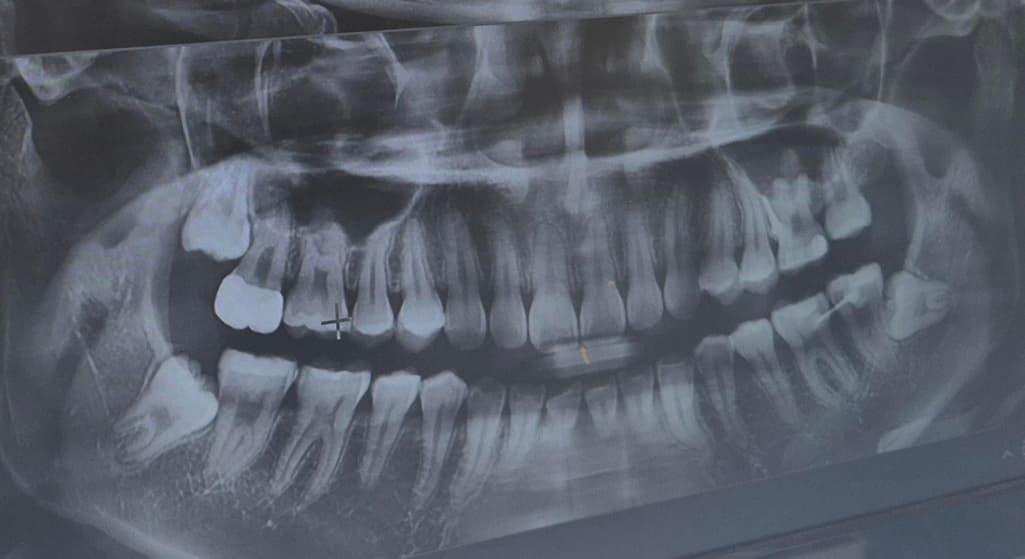

이것 때문에 치과에서 물어봤는데 큰 이상 없다고 해서요 육안으로 또는 엑스레이상으로 문제 있는 게 있을까요? 5개월 전에도 이런 증상 있었고 그때 찍은 거에요

해당 치아 자체에는 그다지 문제가 보이지는 않아서 사랑니로 인한 통증일 확률도 있겠습니다.

육안상으로나 엑스레이 상으로 크게 문제가 잇어 보이진 않습니다. 치아 표면에 교모가 되서 시리다면 추후에 신경치료를 하셔야될수도 있습니다.

오른쪽 밑 맨 뒤 어금니가 문지르면 아파요. -> 사랑니가 영향을 줬을 가능성이 있습니다. 다른 치과도 가보세요안녕하세요. 안상우 치과의사입니다.